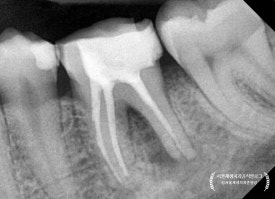

파노라마 엑스레이를 먼저 볼까요?

(정확한 진단에는 전체를 보는 눈이 필수입니다!)

왼쪽 아래 어금니 뿌리 주변이 심상치 않네요...

확대해보겠습니다.

파노라마를 확대해보니,

뿌리 쪽으로 까맣게 뼈가 녹아내린 모양이 관찰됩니다.

보다 정확한 진단 및 상황파악을 위해

치근단엑스레이를 추가로 촬영하였습니다.